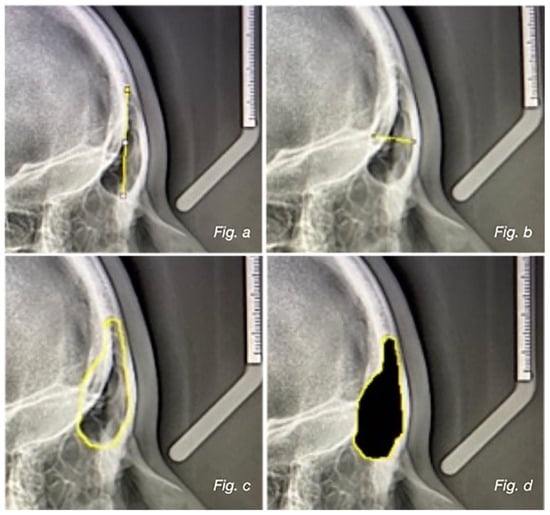

Background: The aim of this work is to compare the size of the frontal sinus and the different skeletal classes and divergence patterns of the subjects. Methods: This study retrospectively includes lateral radiographs performed on a total of 200 adults (78 M, 122

Background: The aim of this work is to compare the size of the frontal sinus and the different skeletal classes and divergence patterns of the subjects. Methods: This study retrospectively includes lateral radiographs performed on a total of 200 adults (78 M, 122 F; mean age 29.2 ± 8.0 years). Subject inclusion criteria were an age of 18–45 years, presence of both frontal sinuses, and good general health with no hormonal system disorders that may affect the growth and pneumatization of the frontal sinuses. Four different parameters of the frontal sinus were evaluated: length, width, perimeter, and area. In order to calculate the variables inherent to the sagittal and vertical skeletal pattern, two independent nominal variables were considered: skeletal class (ANB°) and mandibular divergence (SN^MP°). Results: The statistical analysis showed that there is a statistically significant difference between the frontal sinus dimension and the three skeletal classes. Subjects in group 3 presented significantly higher mean dimensional values. In the analysis of sinus size variables with skeletal divergence, significant results were found for the width value, which resulted in higher average values in group c. Conclusions: The present study shows a statistically significant difference in frontal sinus size among different skeletal classes and divergence patterns. This result suggests that, in future studies, it should be analyzed whether the dimensional analysis of the frontal sinus could be associated with skeletal class III malocclusion.

Figure 1